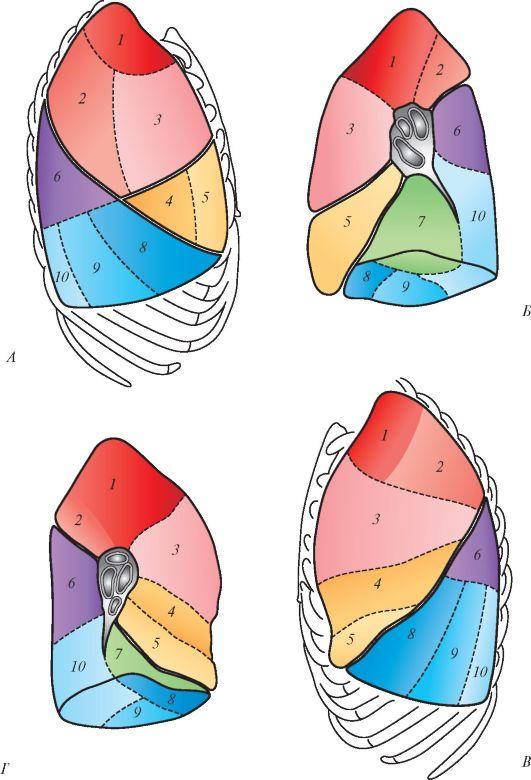

Анатомические изображения сегментов легких различных животных

Раздел: Другие животные